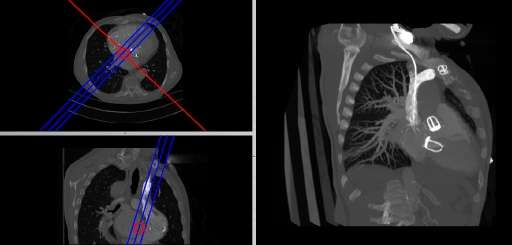

- Coronal and sagittal reconstructions are referred to as Orthogonal MPRs because the perspectives generated are from planes of image data which are at right angles to each other. Composite MPR displays can be generated so that linked cursors or crosshairs can be used to locate a point of interest from all three perspectives, as illustrated in these images:

|

|

- This form of image presentation is sometimes referred to as a TCS display - implying the viewing of Transaxial, Coronal and Sagittal slices. It can be combined with the slice projection methods we discussed earlier, as illustrated in the two sets of images below, where the blue lines highlight the limits of the coronal projections:

- Oblique Reconstruction

- Oblique MPRs are possible by defining angled planes through the voxel data , as illustrated in the following figure:

- Here the plane can be defined in, say, the axial images (red line, top left) and a maximum intensity projection (the limits used are highlighted by the blue lines), for example, can be displayed for the reconstructed plane (right). This technique is useful when attempting to generate perspectives in cases where the visualization of three-dimensional structures is complicated by overlapping anatomical detail.